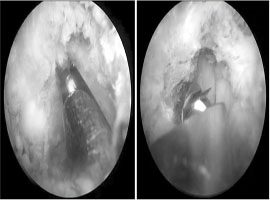

다른 수술법에 비해 지금 시작되고 있는 신의료기술 같은 느낌입니다. 어깨도 과거에는 역사적으로 수술을 거의하지 않는 해부학적 구조물이 었으나, 현대사회에서 사용되는 비율이 높아짐에 따라 현재는 거의 무릎 수준으로 환자가 많은 것 같습니다.

이 처럼 수요가 많지 않다 수요가 폭발한 것 처럼, 척추수술도 생각보다 수술이 간편하고 회복이 빨라지면서 관절경 수술수가 늘어나고 있습니다. 척추도 병변이 미세하게 작은 부분이라면 작은 절개창으로 그 부분만 수술 하므로써 증상 호전이 쉽게 가능하게 된다는 개념입니다.

앞으로 조금 더 지켜봐야겠지만 위와같은 감압술 수술법이 계속 많아질 것으로 생각이 됩니다.

추후에는 척추 내시경 로봇까지도 생각해 볼 수도 있을 것 같네요.